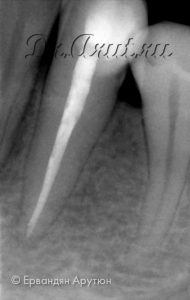

Через год (апрель 2019) была произведена контрольная рентгенография 33 зуба. На рентгенограмме мы видим полное восстановление костной ткани.